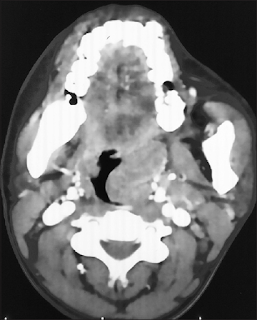

Actinomycotic infections of the head and neck, although fairly uncommon, represent an important entity because of its varied presentation, difficult diagnosis, and long course of treatment. A 20-year-old female presented with throat pain and difficulty in swallowing for 1 year. Examination revealed a Grade IV enlargement of the left tonsil. The patient underwent tonsillectomy, and the postoperative histopathology revealed actinomycosis. Actinomyces is anaerobic filamentous bacteria which are known to colonize as commensals in tonsillar crypts which on histology show an outer zone of granulation tissue and a central zone of necrosis containing many sulfur granules that represent microcolonies of Actinomyces. Actinomycosis of the head-and-neck region is a significant entity because it can mimic other common lesions, especially in the oropharynx. In cases of recurrent tonsillitis and tonsillar hypertrophy, tonsillectomy is the treatment of choice, and histopathological examination of resected tissue is strongly advocated. This report supports the view that Actinomyces may have a causal association with recurrent acute tonsillitis and tonsillar hypertrophy.